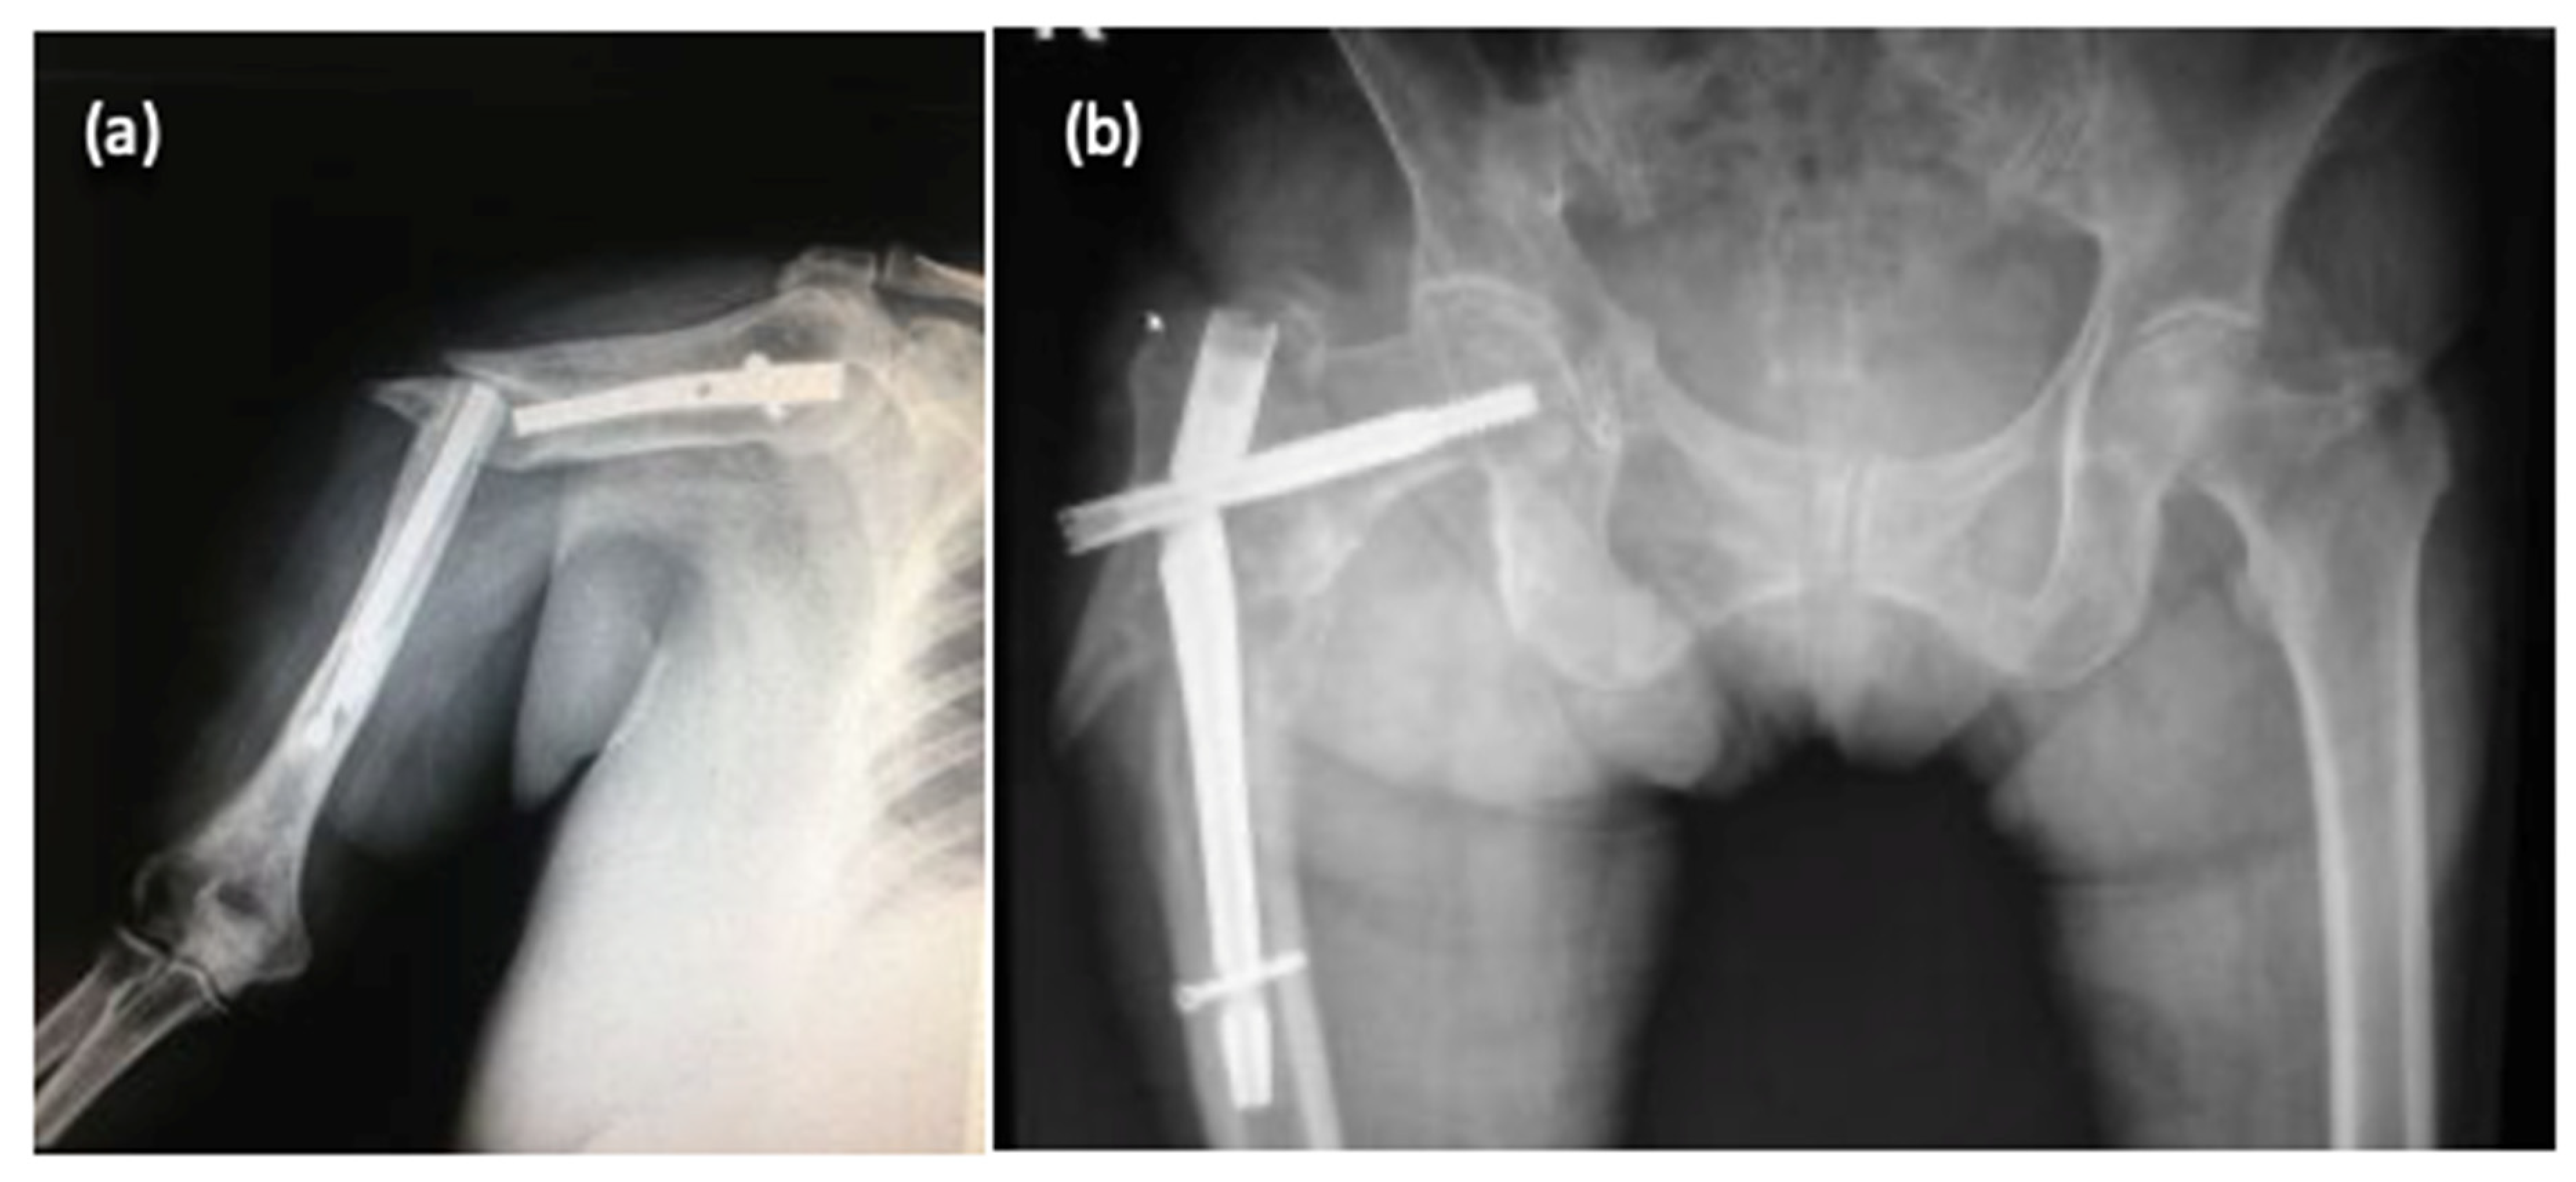

| No. | Patient Age | Fracture Location (Bone Type) | Type of Implant | Failure Causes | ||||

|---|---|---|---|---|---|---|---|---|

| External Factors (Traumatic Event) | Surgical Causes | Implant Defects | ||||||

| Inadequate Implant Size | Deficient Fracture Reduction | Materials Defects | Surface Defects | |||||

| 1 | 36 | Tibia | IMN | (+) | ||||

| 2 | 65 | Femur | IMN | (+) | (+) | |||

| 3 | 72 | Femur | GN | (+) | ||||

| 4 | 26 | Humerus | PS | (+) | ||||

| 5 | 44 | Tibia | IMN | (+) | (+) | (+) | (+) | |

| 6 | 31 | Tibia | PS | (+) | (+) | (+) | ||

| 7 | 71 | Femur | GN | (+) | ||||

| 8 | 67 | Femur | DHS | (+) | (+) | |||

| 9 | 39 | Humerus | IMN | (+) | (+) | |||

| 10 | 78 | Femur | DHS | (+) | ||||

| 11 | 46 | Tibia | IMN | (+) | (+) | (+) | ||

| 12 | 42 | Humerus | PS | (+) | (+) | |||

| 13 | 69 | Femur | DHS | (+) | ||||

| 14 | 18 | Humerus | IMN | (+) | ||||

| 15 | 68 | Femur | DHS | |||||

| 16 | 32 | Humerus | PS | (+) | (+) | |||

| 17 | 74 | Femur | GN | (+) | ||||

| 18 | 59 | Femur | DHS | (+) | ||||

| 19 | 46 | Humerus | IMN | (+) | (+) | |||

| 20 | 55 | Tibia | IMN | (+) | ||||

| 21 | 69 | Femur | DHS | (+) | ||||

| IMN=Intramedullary Nail; GN=Gamma Nail; DHS=Dynamic Hip Screw; PS=Plate-Screw System | ||||||||